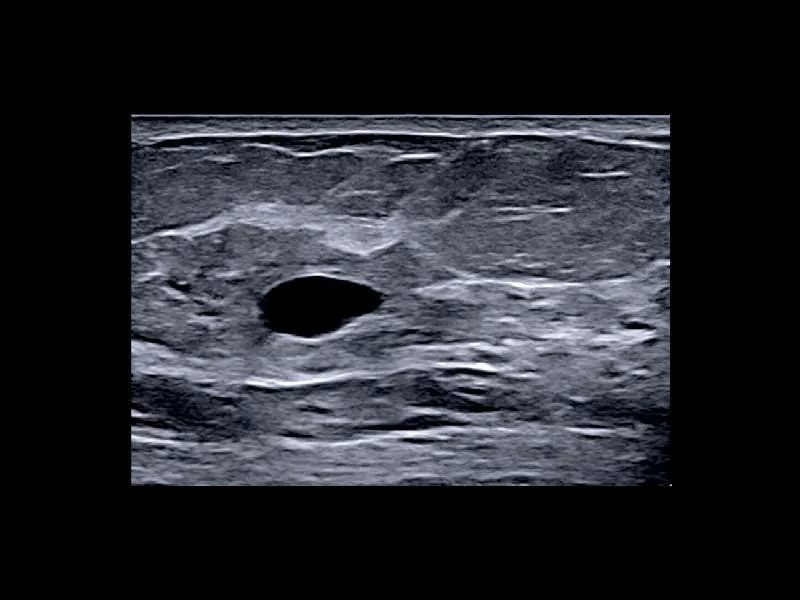

MyLab™X1 - Neck-lump

MyLab™X1 - Neck-lump